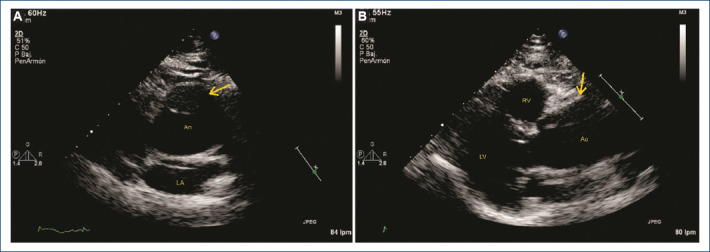

一名慢性肾病患者无症状的斯坦福A型主动脉夹层。

Asymptomatic stanford A aortic dissection in a patient with chronic kidney disease.